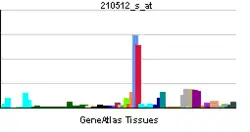

This gene is a member of the platelet-derived growth factor (PDGF)/vascular endothelial growth factor (VEGF) family and encodes a protein that is often found as a disulfide linked homodimer. This protein is a glycosylated mitogen that specifically acts on endothelial cells and has various effects, including mediating increased vascular permeability, inducing angiogenesis, vasculogenesis, and endothelial cell growth, promoting cell migration, and inhibiting apoptosis. Alternatively spliced transcript variants, encoding either freely secreted or cell-associated isoforms, have been characterized.[6]

VEGF-A shows prominent activity with vascular endothelial cells, primarily through its interactions with the VEGFR1 and -R2 receptors found prominently on the endothelial cell membrane. However, it does have effects on a number of other cell types (e.g., stimulation monocyte/macrophage migration, neurons, cancer cells, kidney and epithelial cells ). In vitro, VEGF-A has been shown to stimulate endothelial cell mitogenesis and cell migration. VEGF-A is also a vasodilator and increases microvascular permeability and was originally referred to as vascular permeability factor.

During embryonic development angiogenesis is initiated as mesoderm mesenchyme cells are specified to differentiate into angioblasts, expressing the Vascular Endothelial Growth Factor Receptor (VEGFR-2). As embryonic tissue utilizes more oxygen than it receives from diffusion, it becomes hypoxic. These cells will secrete the signaling molecule vascular endothelial factor A (VEGFA) which will recruit the angioblasts expressing its partnering receptor to the site of future angiogenesis. The angioblasts will create scaffolding structures that form the primary capillary plexus from where the local vasculature system will develop. Disruption of this gene in mice resulted in abnormal embryonic blood vessel formation, resulting in underdeveloped vascular structures. This gene is also upregulated in many tumors and its expression is correlated with tumor development and is a target in many developing cancer therapeutics. Elevated levels of this protein are found in patients with POEMS syndrome, also known as Crow-Fukase syndrome which is a hemangioblastic proliferative disorder. Allelic variants of this gene have been associated with microvascular complications of diabetes 1 and atherosclerosis.

Vascular endothelial growth factor A (VEGF-A) is a dimeric glycoprotein that plays a significant role in neurons and is considered to be the main, dominant inducer of the growth of blood vessels. VEGFA is essential for adults during organ remodeling and diseases that involve blood vessels, for example, in wound healing, tumor angiogenesis, diabetic retinopathy, and age-related macular degeneration. During early vertebrate development, vasculogenesis occurs which means that the endothelial condense into the blood vessels. The differentiation of endothelial cells is dependent upon the expression of VEGFA and if the expression is abolished then it can result in the death of the embryo. VEGFA is produced by a group of three major isoforms as a result of alternative splicing and if any three isoforms are produced (VEGFA120, VEGFA164, and VEGFA188) then this will not result in vessel defects and death of the full VEGFA knockout in mice. VEGFA is essential in the role of neurons because they too need vascular supply and abolishing the expression of VEGFA from neural progenitors will result in defects of the brain vascularization and neuronal apoptosis. Anti-VEGFA therapy can be used to treat patients with undesirable angiogenesis and vascular leakage in cancer and eye diseases but also could result in the inhibition of neurogenesis and neuroprotection. VEGFA could be used to treat patients with neurodegenerative and neuropathic conditions and also increase vascular permeability which will stop the blood-brain barrier and increase inflammatory cell infiltration.[7][8][9]